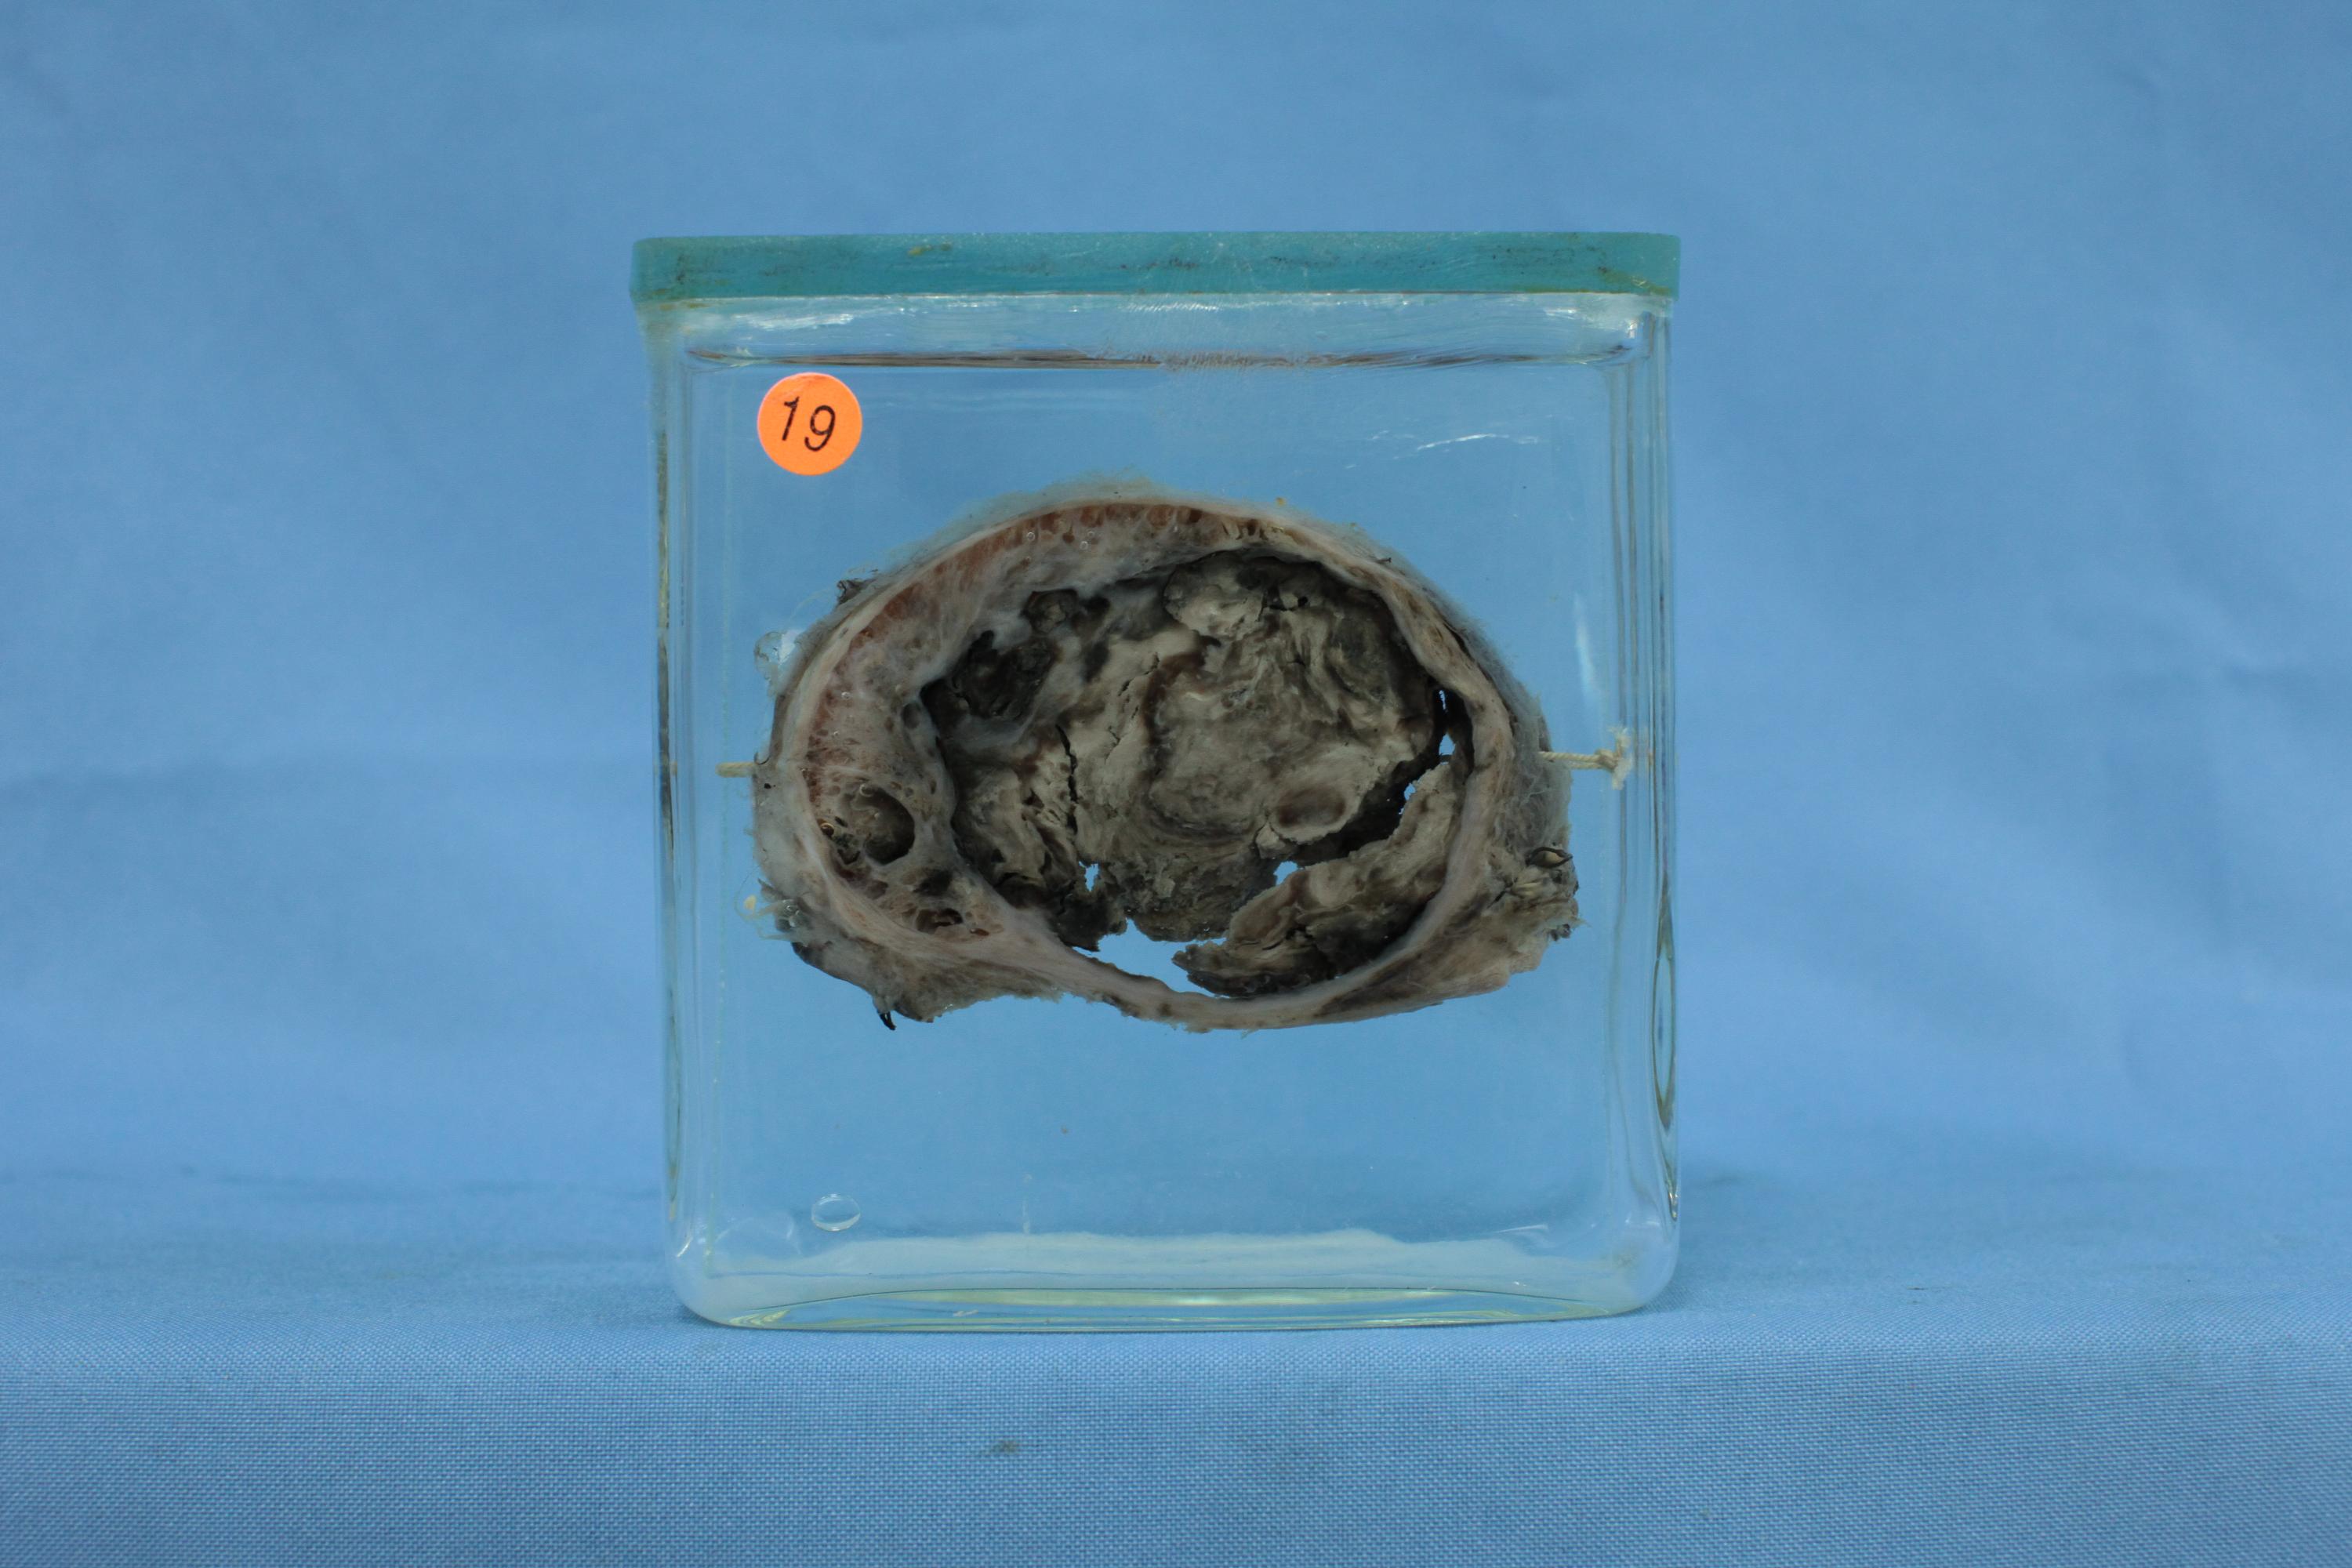

内分泌-69-19. 甲状腺腺瘤伴退行性变

患者女,59岁,部分甲状腺组织,内见一圆形结节,直径6cm,包膜完整,质实、伴大量出血、坏死。